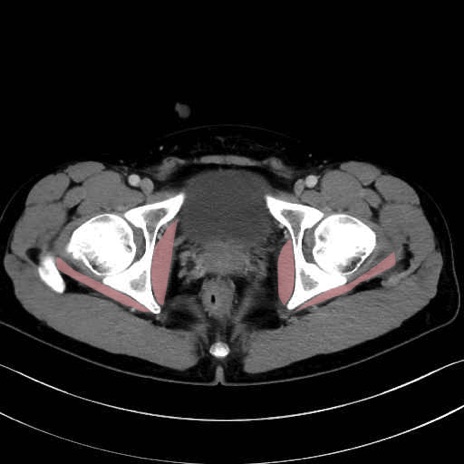

内閉鎖筋(obturator internus) のCT画像の解剖

内閉鎖筋 (Obturator internus)